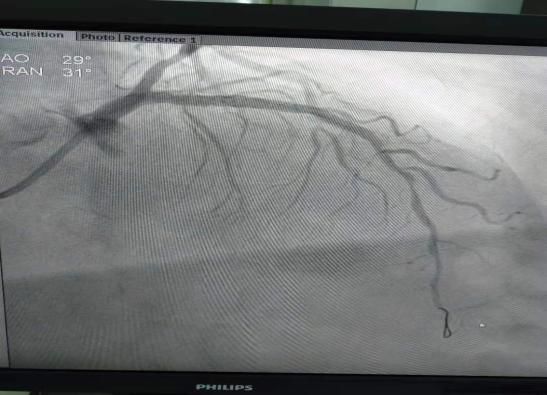

(2)2018年11月2日开展第一例冠状动脉造影术。

患者:孙某  女性48岁 超化镇

图片

术前

术后